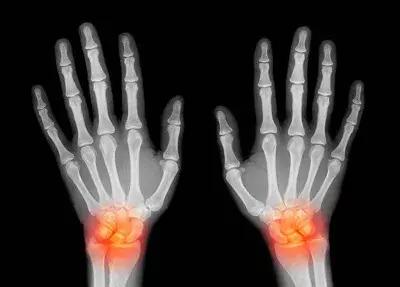

神经损伤更多见的是慢性神经劳损,而且往往不容易发现。和手部相关的慢性神经损伤多见于肘部和腕部。慢性劳损后局部增生、骨折后畸形愈合、先天性结构异常或局部长肿物均可能导致神经通路变窄,在关节活动的时候,受压的神经与周围的结构不断摩擦,比较容易发生局部水肿、增粗,又进一步加重了神经卡压。

手麻、痛、不灵活需警惕

神经受损都会有麻、痛、活动不灵活等表现。一旦察觉有这样的症状,应该立即到正规医院的相关专科就诊,尽早治疗。专家表示,神经损伤早发现早治疗效果会比较好。

怕就怕开始不引起注意,好比一些人长时间打电脑或搓麻将后觉得手麻,甩甩手后有点缓解就了事,结果耽误了治疗时机,等到肌肉萎缩了再想恢复就相当难了。

神经出问题往往恢复慢,有的甚至很难恢复,无法逆转,因此要强调早期发现和治疗。